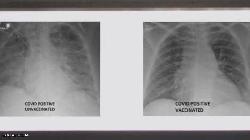

​كورونا واللقاح.. دليل علمي جديد على أهمية التطعيم

2021-08-0311:05 1831